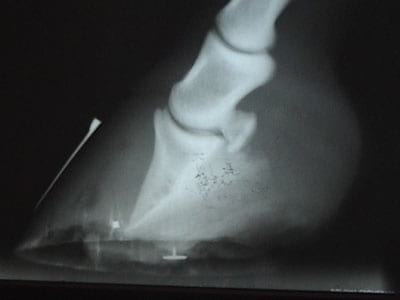

Fig. 2. La imagen de la izquierda muestra como se toma una radiografía con puntos de referencia. La imagen central muestra la rotación de la falange, el espacio donde se presenta la separación laminar y la necrosis de la palma. En la imagen de la derecha hay una rotación que casi llega a la vertical (equino del video) con deformación de la tercera falange y signos de osteomalacia.

El manejo terapéutico de la laminitis debe tener como fundamento la prevención del daño anatómico, evitando o disminuyendo al máximo la necrosis de la unión dermo-epidérmica; esto se logra provocando la vasoconstricción de las anastomosis arteriovenosas y de esta manera, recuperar el flujo sanguíneo capilar; para lograr lo anterior, sometemos los cascos del caballo a crioterapia, sumergiéndolos en agua con hielo (8-10° C) durante dos horas 3-4 veces en el día, durante los primeros 5 días, inclusive, si es necesario, se sumergen los cascos en agua con hielo por 24-36 horas seguidas. El segundo paso es el de atacar los desordenes que dieron inicio a la enfermedad; en el caso de sobrecarga por concentrados, se debe suministrar por medio de sonda naso-gástrica aceite mineral en proporción de 2-4 litros, dependiendo del peso del caballo, repitiendo la dosis a las 2 horas, de ser necesario. Aplicar un antimicrobiano para controlar la proliferación de flora bactriana dañina, especialmente el Staphilococcus bovis. Se deben controlar los procesos infecciosos que se presenten; si hay presencia de cólico o accidentes intestinales, metritis, pleuritis, colitis o reaaciones a medicamentos, se deben seguir los protocolos correspondientes a cada entidad en particular. Así sucesivamente con cualquier anomalía que pueda desencadenar la Laminitis. El tercer paso es el de disminuir el dolor sin suprimirlo totalmente, utilizando AINES en concentraciones ajustadas al peso del caballo; el AINE de mayor utilización es la fenilbutazona a dosis de 1.1 mg/kg como dosis inicial, continuando con la mitad de la dosis cada 12 horas por 4 días, y terminando con 0.5 mg/kg cada 24 horas por 8 días. Este AINE se puede combinar con otros pero se debe tener mucho cuidado con las dosis y la frecuencia de suministro. Es muy importante tener en cuenta que cualquier AINES interfiere con la producción de prostaglandinas, para lo cual debemos proteger la mucosa gastrointestinal de la acción de los jugos gastro-entericos por la disminución de la prostaglandina E2. El cuarto paso es el de darle apoyo mecánico a la tercera falange para evitar o disminuir el grado de desplazamiento distal o de rotación, usando una herradura de corazón ajustable con barra delantera; esta herradura debe ser elaborada por un herrador competente bajo la supervisión de un Veterinario, y debe forjarse y ajustarse con base a radiografías previas, en lo posible tomadas inmediatamente antes de ejecutarse el herrado (Fig. 2).